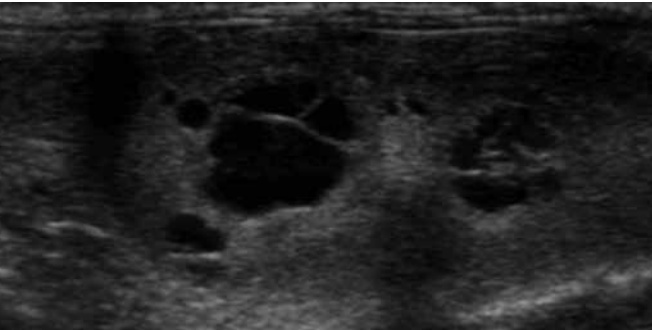

5-2. 다낭성 신장질환(Polycystic kidney disease; PKD)(그림 9)

다낭성 신장질환(PKD)은 고양이에서 가장 흔한 유전 질환 중 하나이며, 호발 품종은 Persian, Ragdoll, Domestic short-hair 종입니다. 임상적 특징은 젊은 성묘, 중년의 성묘에서 현저한 신장 비대를 보이며, 결국은 만성신장질환으로 진행됩니다.

초음파 영상의 특징은 다양한 크기의 얇은 벽에 무에코 낭종이 피질, 피질~수질의 경계부위, 수질 부위에 나타납니다. 작은 낭종은 해상도의 한계로 놓칠 수도 있습니다. 간, 췌장에 낭종 동반 가능성도 있습니다.